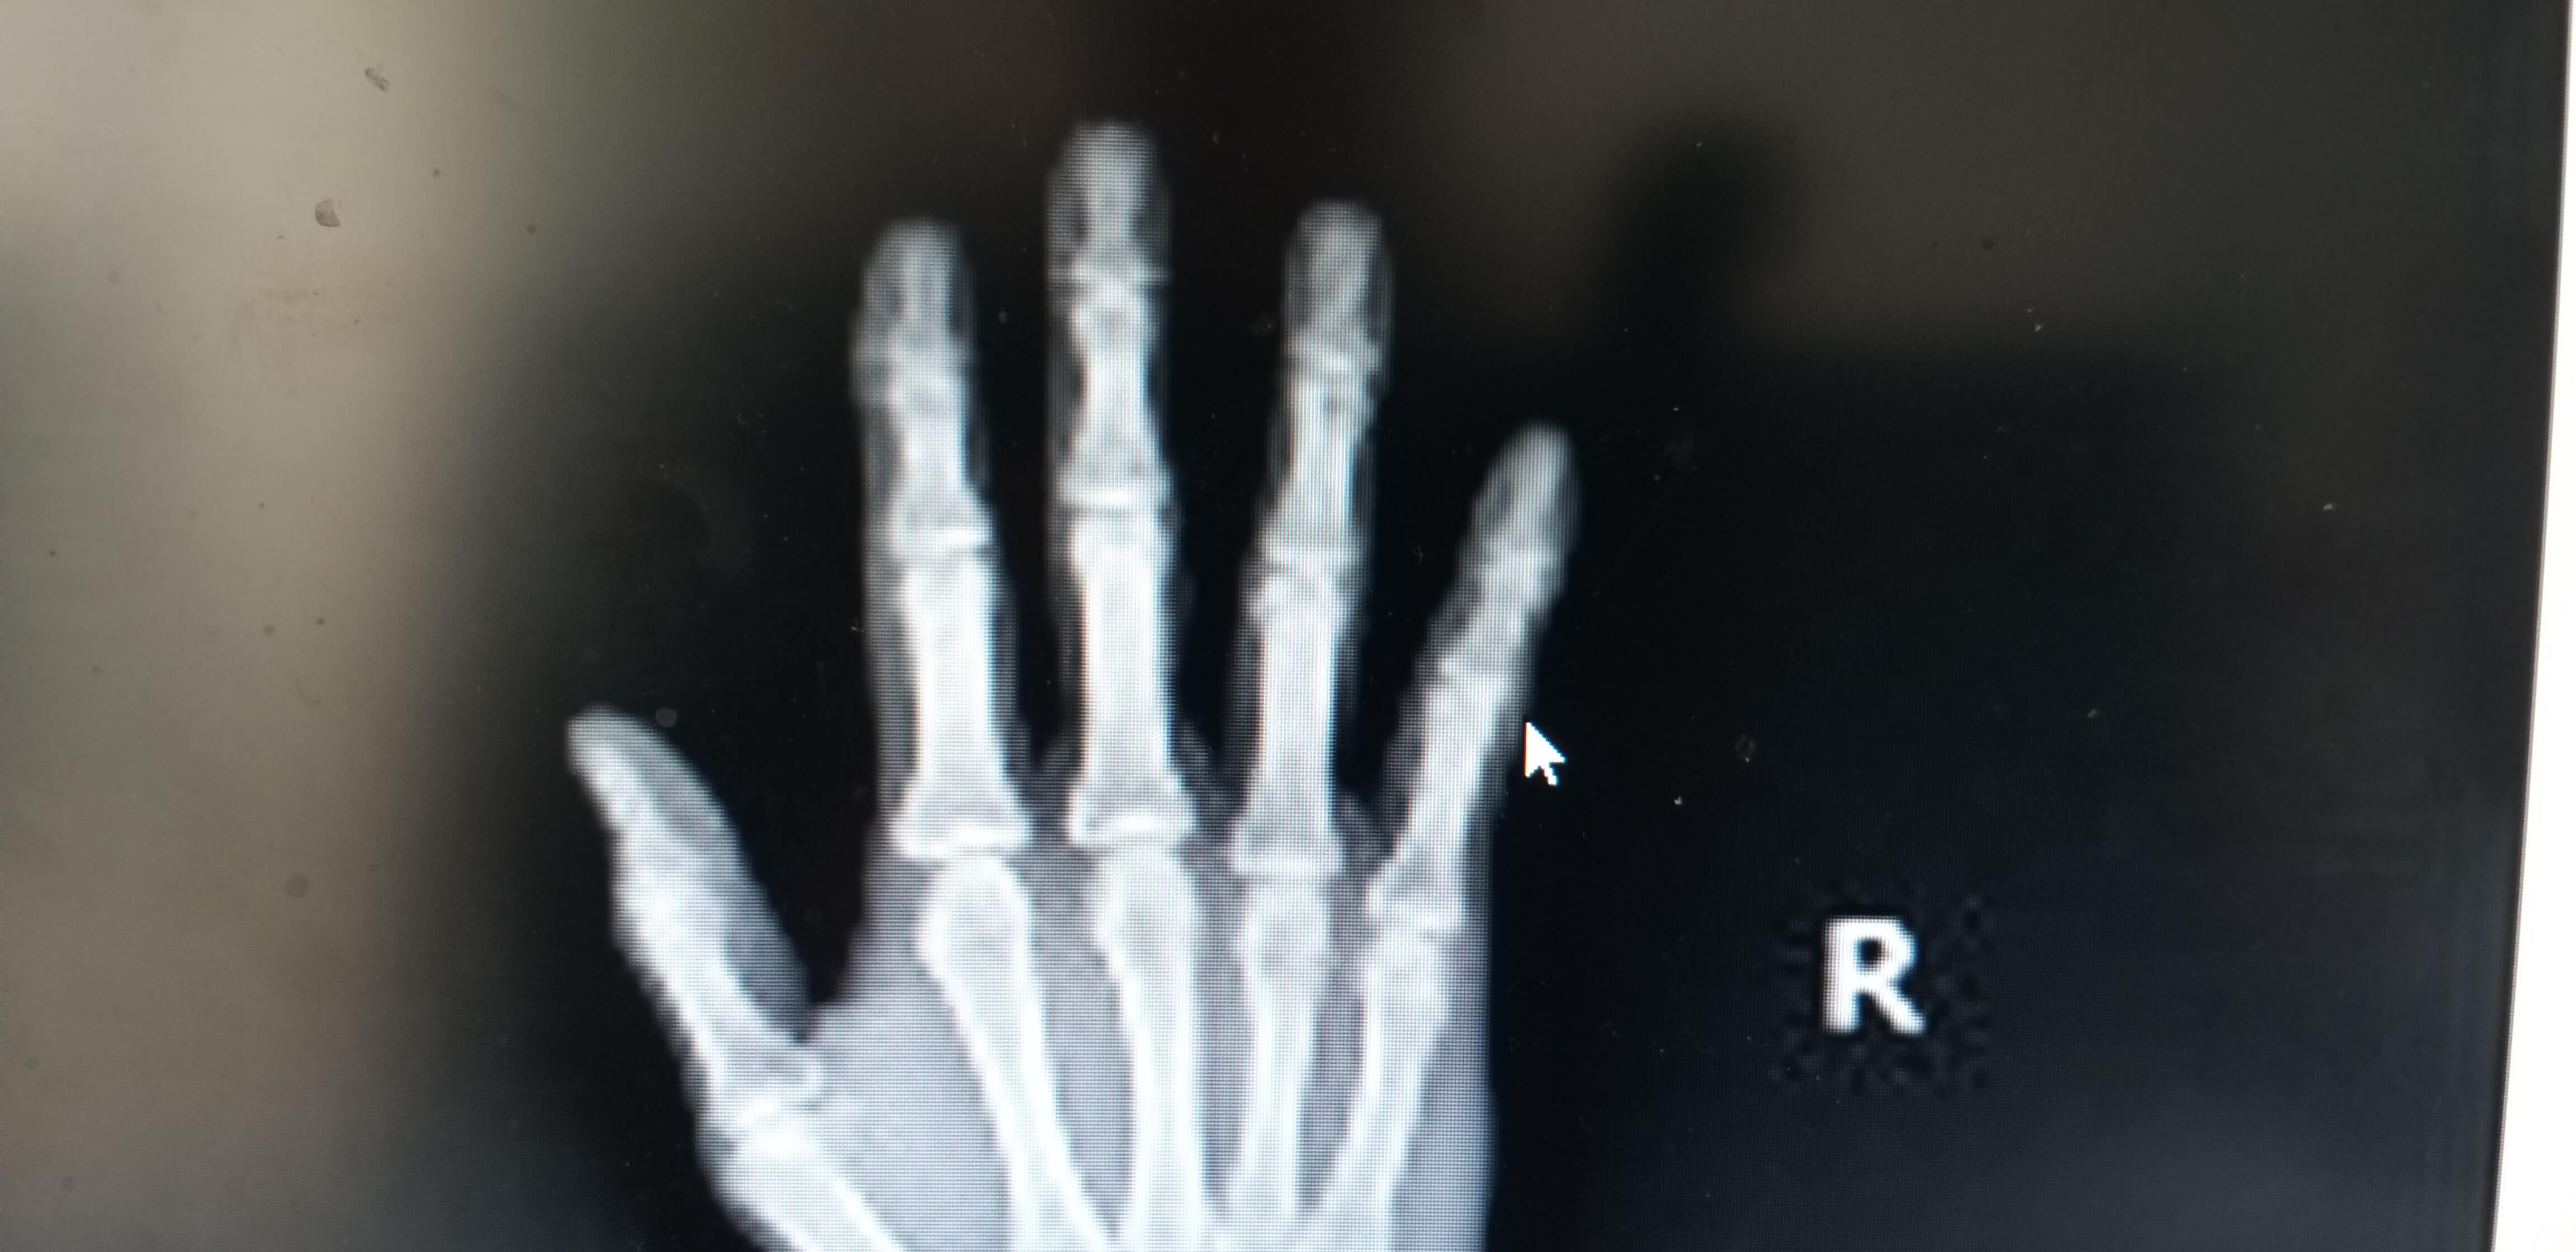

다친사진 및 경과를 모두 설명드렸고 이전병원에서의 사진을 보여드렸고 다시 X-RAY 사진촬영을 하신후 진단받은 결과로는 손가락 인대파열은 엄지손가락 말고는 기본적으로 보존적 치료를 먼저 한다고 말씀하셨습니다.

뼈조각은 크기나 형태에 따라 문제가 발생되지 않아보이고 새끼손가락의 배열도 잘맞아서 수술은 권유하지 않았습니다.

한달동안 부목을 손가락에 고정시키고 상태를 확인해보자고 말씀하셔서 이게 도대체 무슨일인지 마음속으로는 다행이라고 생각하고 몇번을 수술안해도 되냐고 물었습니다.